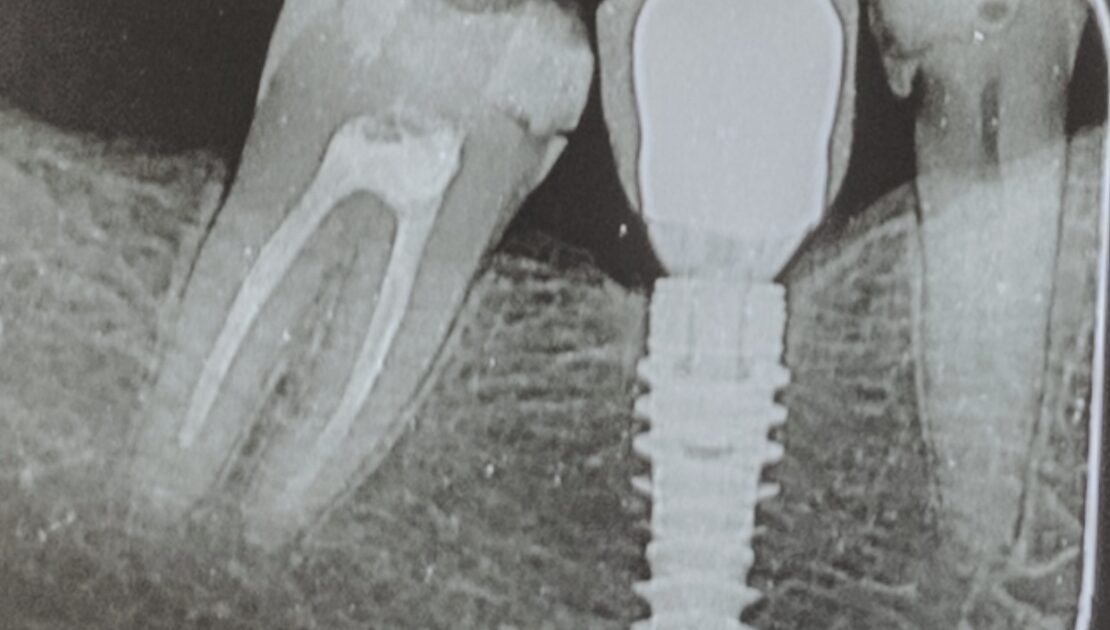

4. Pérdida de hueso (lo vemos con radiografías)

A veces, el hueso alrededor del implante empieza a retraerse sin causar síntomas.

Por eso, en Vadenta, realizamos controles radiográficos periódicos. Gracias a ellos, podemos detectar la pérdida de hueso en fases muy tempranas y actuar antes de que haya daño.